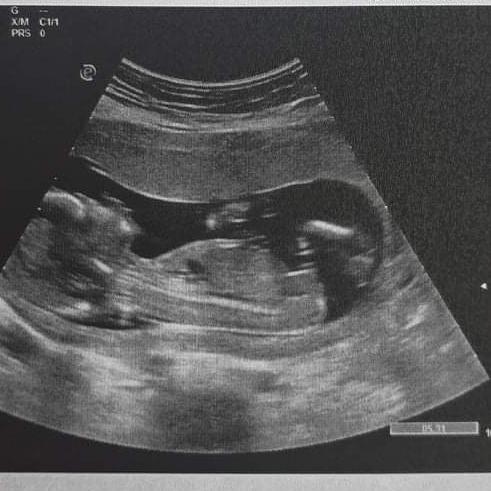

Atrezia tenkého čreva

- Atrezia tenkého čreva má stim nikto skúsenosť poraďte mi môj syn je 35 týždňov predčasný narodení mal opracija ťenkeho čreva mal veľmi tenké črevo Mišík ísť na operáciu to črevo mu virezali neprechodne má terás vivod opracija mu spravili Košiciach Chirurg Griboš bol tam tri týždne terás je na dedske nemocnici v Prešove ale taško mi preberá má mať druhu opraciju aby mu spojili čreva aby nemal vivod ale pirate mi keď niekto má stim skúsenosť lebo sa bojím us má dve mesiace